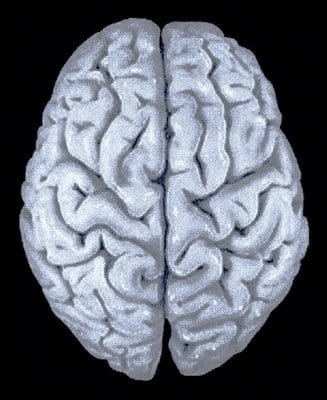

Hablemos del cerebro

¿Hablamos de dolor? Hablemos de cerebro. No se necesita enfermedad. Basta con considerar los errores.

Erase una vez un cerebro humano… Era un cerebro sano, ávido de información…

– ¿Por qué creéis que os duele? El dolor es una decisión cerebral. ¿Por qué pensáis que puede decidir el cerebro que duela un fin de semana, cuando se acerca la regla, cuando toca viajar, con el chupito de champán o sin motivo aparente?